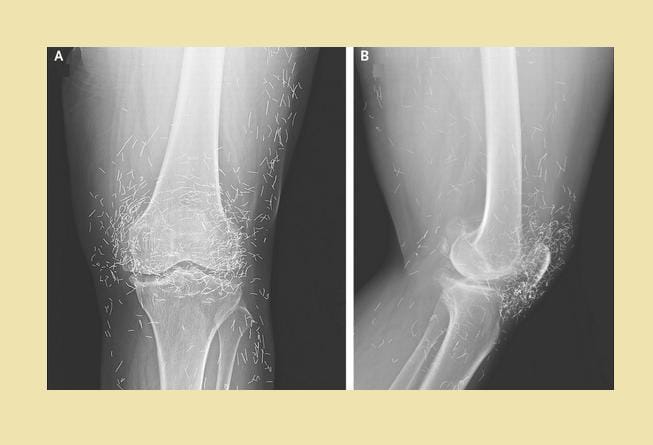

1. Ratusan susuk terlihat jelas lewat hasil foto sinar-X

Dalam unggahannya itu, Tasqia menuliskan bahwa ia sedang menangani seorang pasien berusia 55 tahun yang ingin melakukan X-ray atau sinar-X. Tak disangka, hasil foto sinar-X pasien tersebut memperlihatkan ratusan atau bahkan ribuan benda asing berbentuk seperti jarum yang bersarang pada tubuh pasiennya itu. Tasqia pun menyebut benda tersebut sebagai susuk. Sangking banyaknya, Tasqia pun tak tahu pasti berapa jumlah susuk yang ada pada bagian tubuh pasiennya itu.

"Pasien wanita, usia 55 tahun mau di X-ray. Nah kalo ini susuknya ada berapa? Itung sendiri deh ya :)," tulis Tasqia.

Menurut Tasqia, dalam bahasa Inggris, ia menyebut susuk sebagai charm needle. Hal ini lantaran bentuknya yang seperti jarum. Susuk juga menurut Tasqia bisa berubah posisi ketika dilakukan foto sinar-X lagi.

"Masih banyak yang gatau susuk ya wkwkw bahasa inggrisnya 'charm needle' karena bentuknya juga kayak jarum. Biasanya kalo di foto X-ray lagi, nanti berubah posisinya," tulis Tasqia.

"Dosen aku yang ngalamin langsung katanya pas lagi bedah di X-ray ada jarum, pas dicari ga ketemu, di foto lagi, tau2 pindah tempat, sampe berkali2, nah loh ;)," lanjutnya lagi.

Meski memiliki bentuk fisik dari logam, Tasqia menyebut bahwa kasus komplikasi karena susuk jarang terjadi. Penemuan susuk oleh dokter dalam tubuh pasien juga bisa disebut sebagai sebuah ketidaksengajaan. Anehnya, susuk yang terlacak lewat foto X-ray seringkali tak ditemukan saat dilakukan pembedahan.

"Susuk ini jarang menyebabkan komplikasi, jadi biasanya pas di X-ray tuh kek "ga sengaja" ketemu. Di X-ray ada, tapu kalo dibedah ga ada gituuuu," ujarnya.